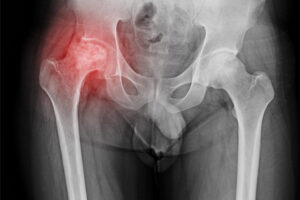

Introduction Avascular necrosis of hip is a serious condition. It happens when blood stops reaching the hip bone. Without enough blood, the bone tissue dies.

Total hip replacement is a common surgery that helps people with severe hip pain. Many people choose this procedure when other treatments do not work.